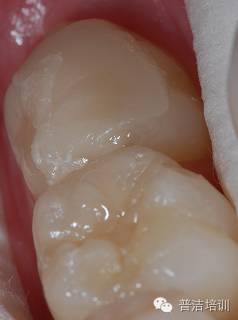

检查咬合 调牙合

抛光完成

【前后对比】

术前

术后

小结:

1、对于一部分牙合面形态完整的病例,印章法是很好的充填方式,临床上有较多的适应范围。

2、树脂充填无论比色,备洞,隔湿 抛光,各方面的细节都非常重要,只有每一步都做好了才可能做出优秀的病例。